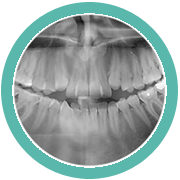

PANORÁMICA

Es una técnica radiológica que representa, en una única película, un imagen general de los maxilares, la mandíbula y los dientes.